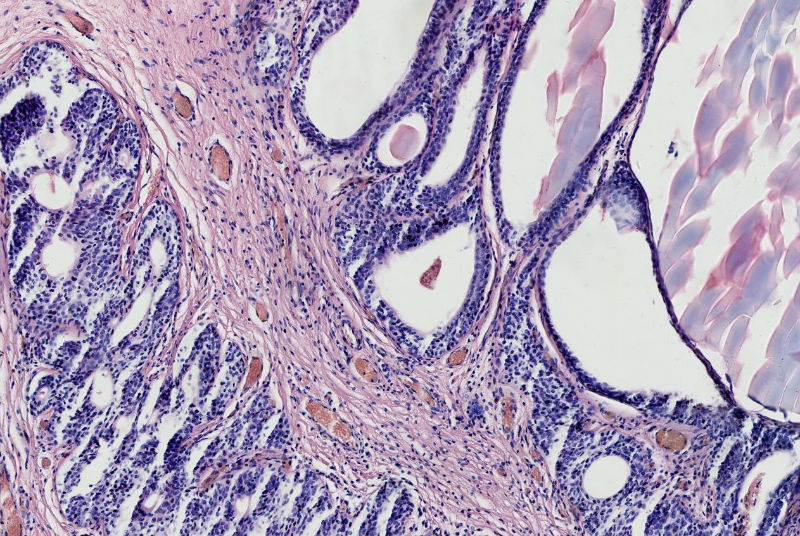

女57岁发现尿道外口息肉二周

上皮下间质中有淋巴细胞浸润,移行上皮巢团中央有柱状上皮围成的腺样腔隙。诊断:腺囊型尿道炎。

腺囊性尿道炎

支持腺囊型尿道炎